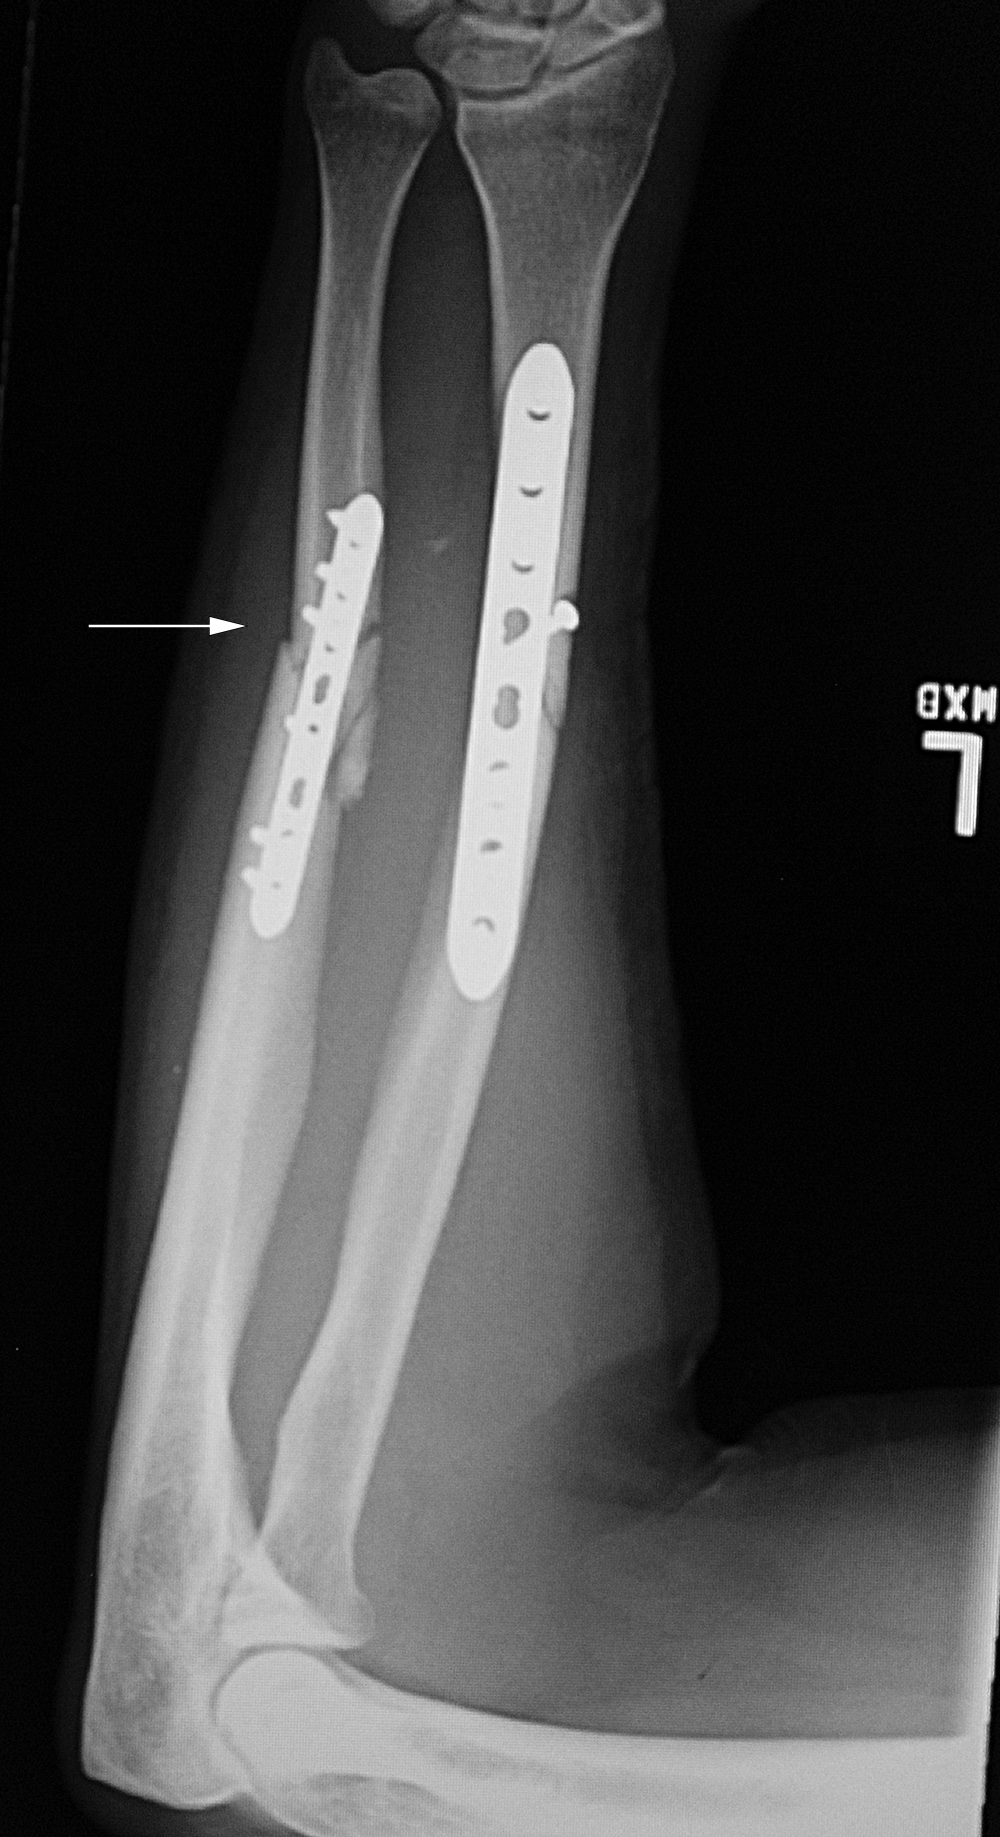

Left tibia stress fracture after fibular fracture fixation |

A short one-third tubular plate and screws plus interfragmentary screw stabilize a healing distal fibular fracture. An associated stress fracture (arrow) is in the distal tibial metaphysis from altered weight-bearing from the fibular fracture. |